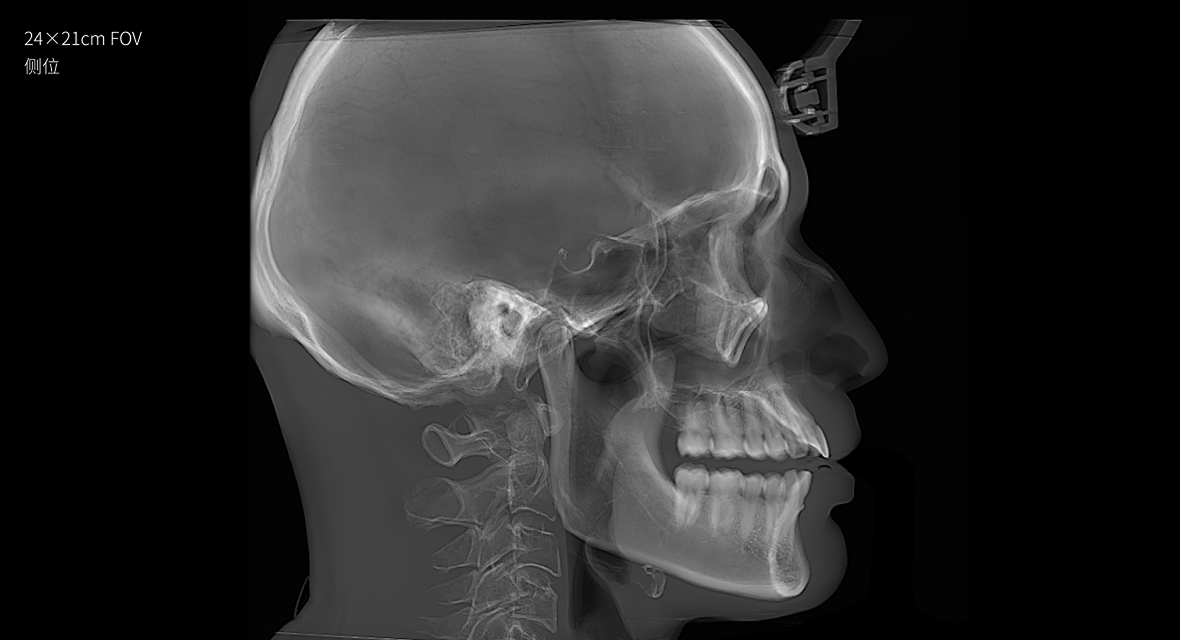

• 超大视野

24×21cm超大视野,口腔颌面一览无余

24×21cm

非拼接超大视野